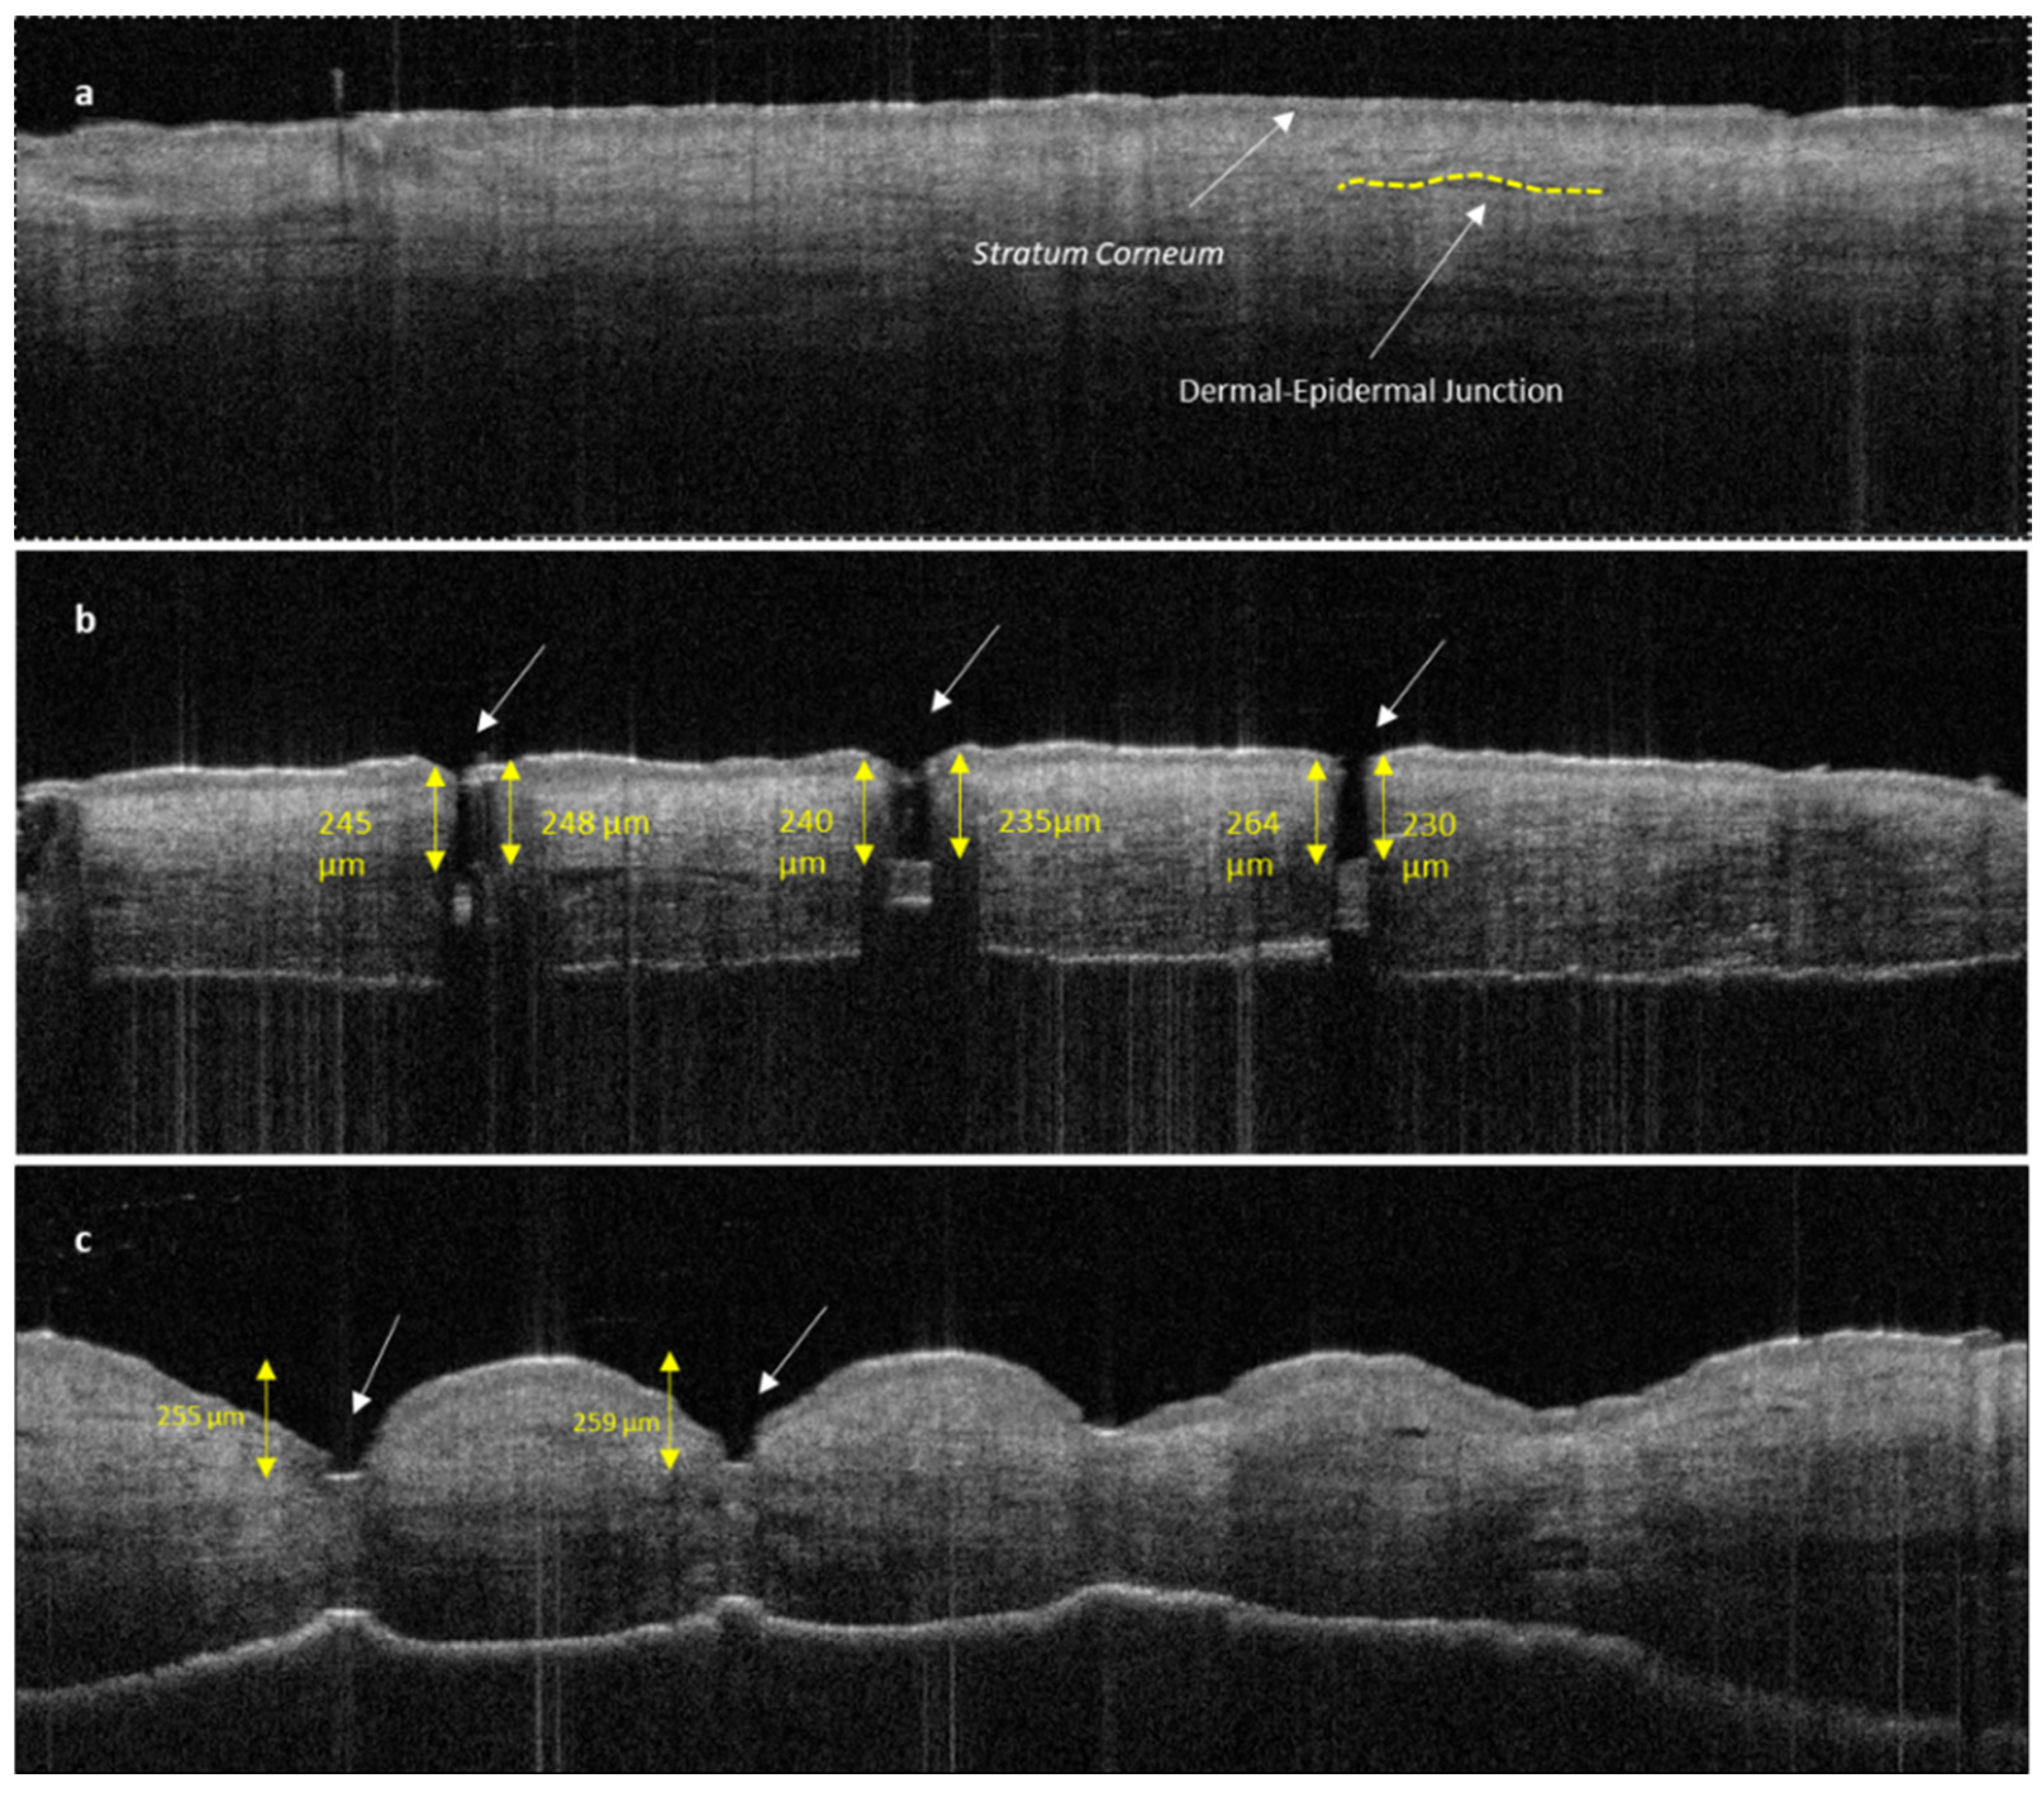

3.2.2. Penetration Efficacy of Microneedles Using Optical Coherence Tomography (OCT)